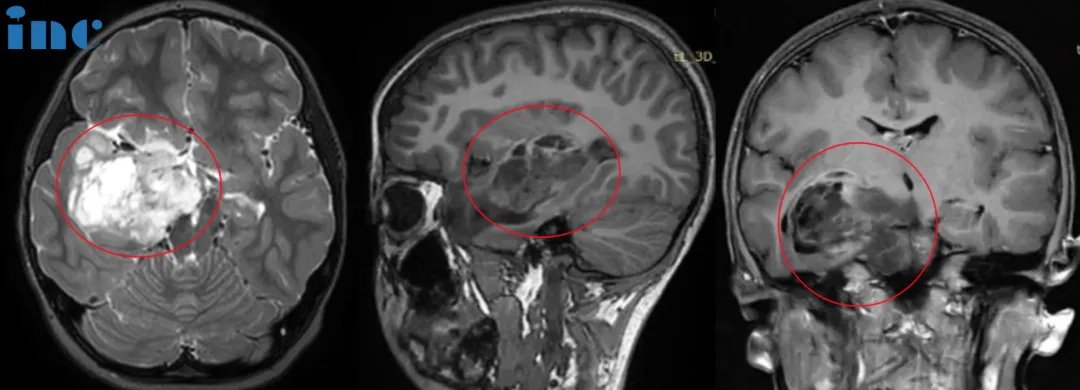

▼可可术前术后影像对比

可可术后病理结果为WHO1级胶质瘤,这代表着预后很好,可以长期生存。术后1年,巴教授示范手术期间,我们再次见到了可可。她还是那么活泼可爱,充满活力。早已回到了校园的她,爱跳舞,和妈妈一起做瑜伽……术后随访的结果也令可可父母非常满意。